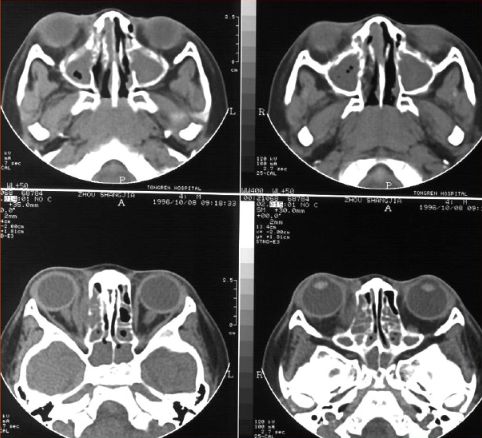

急性鼻窦炎

筛窦异物伴急性感染